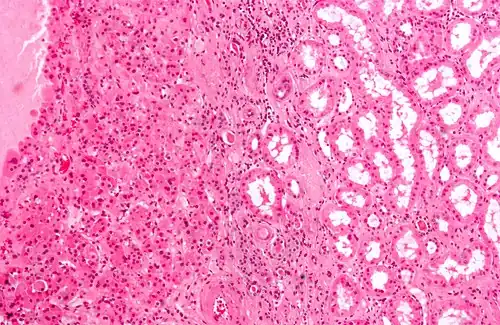

O oncocitoma renal é caracterizado pela presença de células epiteliais grandes e intensamente eosinofílicas, organizadas em um estroma de ilhotas em meio ao tecido conjuntivo frouxo; outros padrões arquiteturais incluem tubular, microcístico, macrocístico e sólido.[2] Mitoses são raras e não há mitoses atípicas, sem presença de necrose coagulativa e, alguns dos oncocitomas renais podem ter invasão perivascular ou no tecido adiposo perirrenal, ainda que seja benigno.[2]